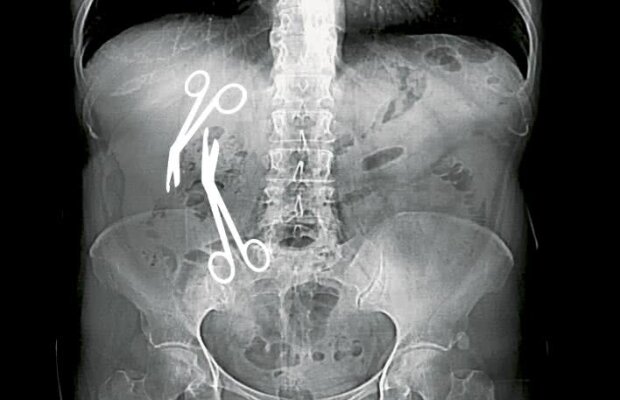

Doctorul Ciomu al femeilor - după ce a uitat două foarfeci într-o femeie, chirurgul Ștefan din Constanța a cusut defectuos o pacientă, astfel încât „trei ani nu am putut să fac nici măcat un control ginecologic”

Directorul medical al Spitalului Militar din Constanța a uitat două foarfeci de 16cm în abdomenul unei paciente de 61 de ani!